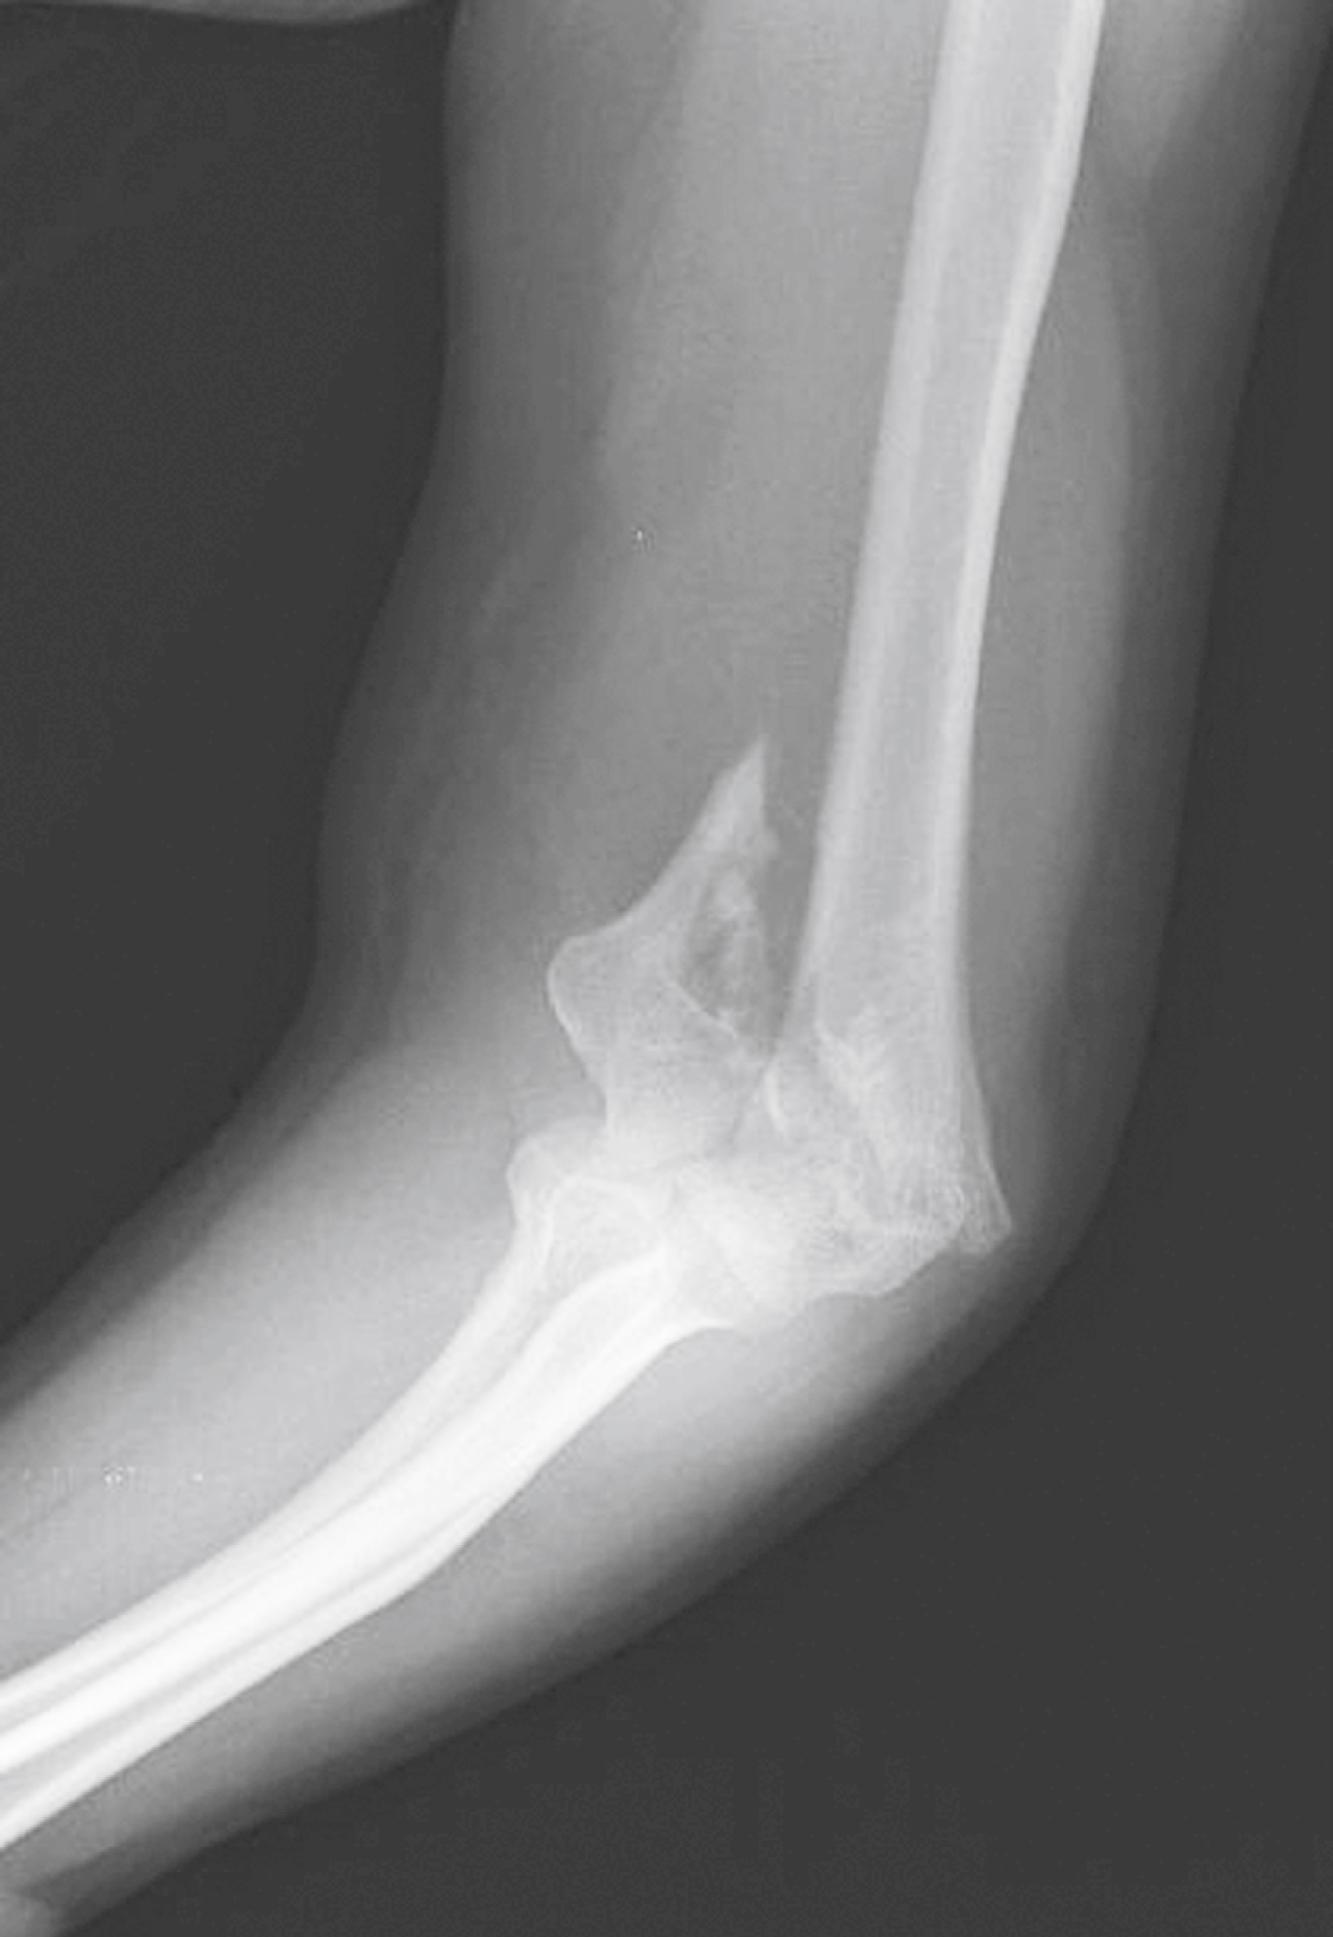

Fig. 44.11, Supracondylar fracture (arrow) with anterior and posterior fat pad.

Extension supracondylar fractures occur as a consequence of a fall on the outstretched hand when the elbow is either fully extended or hyperextended (e.g., a fall off the playground “monkey bars”). The strong action of the triceps tends to pull and displace the distal fragment in a posterior and proximal direction. In children with extension-type supracondylar fractures, the arm is held at the side and has a characteristic S-shaped configuration, whereas with flexion-type supracondylar fractures, the forearm is supported with the opposite hand with the elbow flexed to 90 degrees. There may be anterior angulation of the sharp distal end of the proximal fragment into the antecubital fossa, which could injure the brachial artery and median nerve ( Fig. 44.10 ). In most cases, however, the brachialis muscle protects the anterior neurovascular structures from injury. Because this fracture primarily occurs in children, 25% of supracondylar fractures are of the greenstick variety, with the posterior cortex remaining intact. Subtle changes (e.g., the presence of a posterior fat pad or an abnormal anterior humeral line) may be the only radiographic clues to the presence of a fracture ( Fig. 44.11 ). Ten percent of children lose the radial pulse temporarily, most often as a result of swelling and not direct brachial artery injury. Fracture reduction, avoiding flexing the elbow more than 90 degrees, and elevating the arm help prevent secondary obstruction to arterial flow. Nerve injuries occur in approximately 10% of these injuries, but the incidence increases to a range of 20% to 50% with increasing severity of fracture displacement. , The anterior interosseous nerve is the most commonly injured, followed by the radial, median, and ulnar nerves. Most deficits seen at the time of injury are neurapraxias that resolve with rest and conservative management. Motor function returns within 7 to 12 weeks, whereas recovery of sensation may take over 6 months, though the recovery of injuries with multiple nerve injuries may take longer than that of isolated nerve injuries. ,

Two diagnostic aids in evaluating for possible supracondylar fractures include using the anterior humeral line and evaluation of Baumann’s angle. The anterior humeral line is a line drawn on a lateral radiograph along the anterior surface of the humerus through the elbow. Normally, this line transects the middle third of the capitellum ( Fig. 44.12 ). With an extension supracondylar fracture, this line either transects the anterior third of the capitellum or passes entirely anterior to it. An abnormal relationship between the anterior-humeral line and capitellum may be the only radiographic evidence of a minimally displaced supracondylar fracture and is a presumptive finding of a fracture. Baumann’s angle is the intersection of a line drawn on the anteroposterior film through the midshaft of the humerus and the growth plate of the capitellum defines an angle of approximately 75 degrees ( Fig. 44.13 ). Radiographic evaluation of the elbow in children is challenging because of the presence of multiple ossification centers ( Fig. 44.14 ). Comparison views of the uninjured elbow are often helpful in distinguishing fractures from the normal epiphyses and ossification centers. Table 44.2 lists the typical age of first appearance and fusion of ossification centers.

Fig. 44.12, (A) A line drawn down the anterior surface of the humerus on a lateral film should transect the middle third of the capitellum. (B) With an extension supracondylar fracture, the line passes more anteriorly.